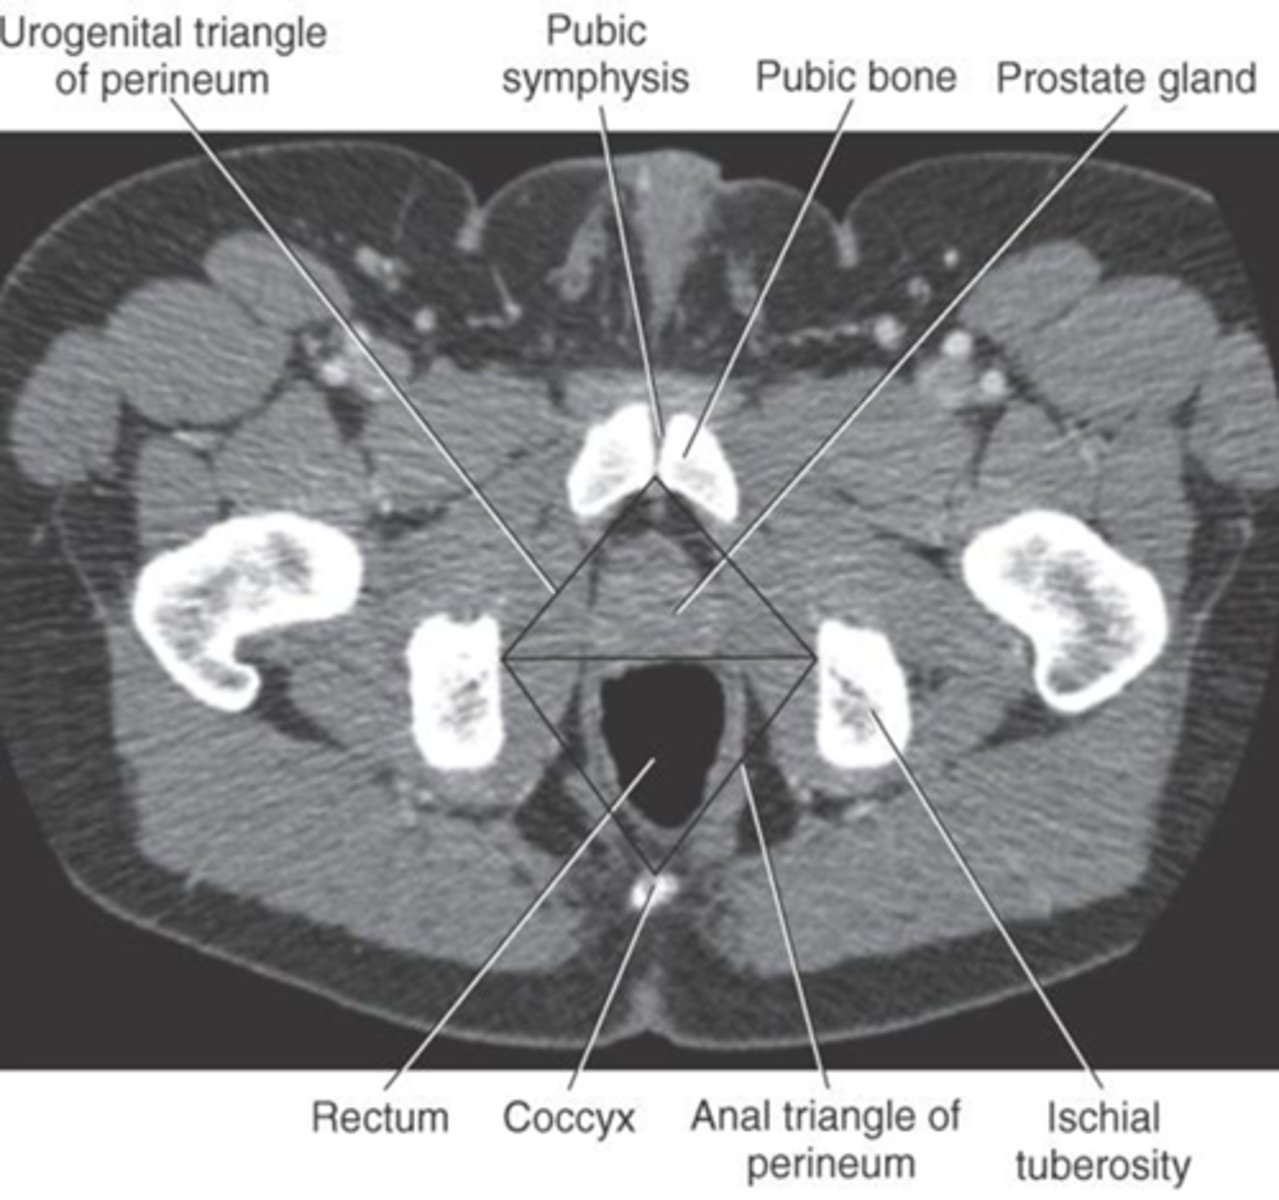

1) Pubic symphysis

2) Pubic bone

3) Prostate gland

4) Rectum

5) Coccyx

6) Ischial tuberosity

Name all numbered structures

1) Pubic symphysis

2) Pubic bone

3) Rectum

4) Coccyx

5) Ischial tuberosity

Name all numbered structures